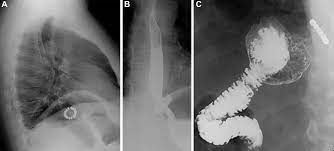

LINX Reflux Management System

LINX reflux management system is indicated in severe cases of gastroesophageal reflux disease. Image via: https://www.jnjmedicaldevices.com/en-EMEA/product/linx-reflux-management-system